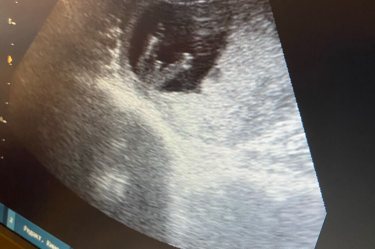

Похож на мальчика, а так может и пуповина лежать так

Тут явный мальчик

я то тут вижу отчетливо пацана но говорят же на этом сроке они одинаковые и можно узнать только по градусу и наклону

Вероятнее мальчик

Мальчик

Мальчик))

14 недель рановато)) у меня так же было с дочкой ? думали с мужем тоже мальчик)) на 20 неделе и на 30 уже девочка говорили) так и родилась ?

Попалась ужасная узистка, она начала читать натацию что в этом сроке нельзя говорить пол, тип может быть не правда зачем врать? до сих пор помню) но конечно все индивидуально)

Потерпите ещё 5 недель и точно узнаёте наверняка))

В таком ракурсе не смотрят

А так на мальчика похоже

Мальчик))у меня тоже так показал, родился сын

Мальчик ?